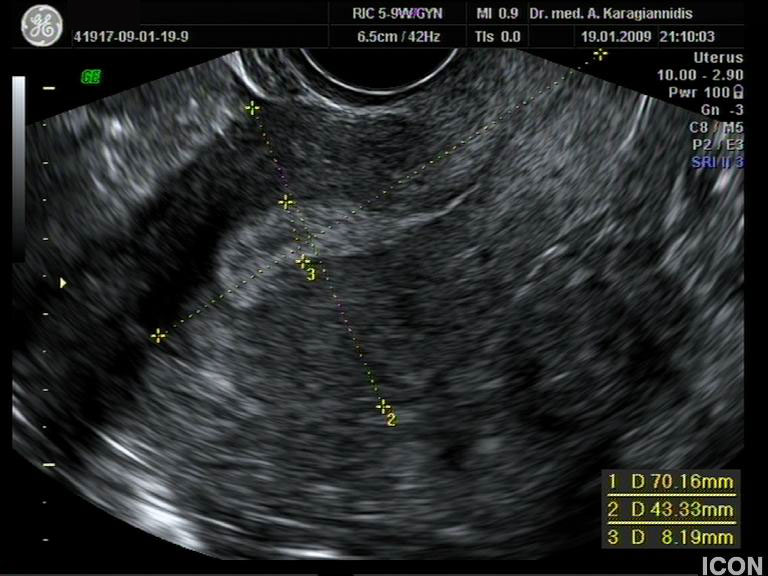

Αυχενική διαφάνεια

Η αυχενική διαφάνεια (ΑΔ) είναι η συλλογή υγρού στον τράχηλο του εμβρύου και συγκεκριμένα ανάμεσα στο δέρμα και στους ιστούς που καλύπτουν τη σπονδυλική στήλη.